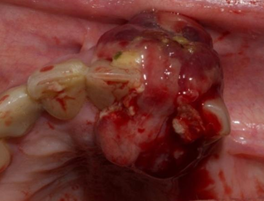

Al examen local, se aprecia parcialmente desdentada superior e inferior. Se observa una tumoración localizada en reborde alveolar maxilar izquierdo, que involucra desde la pieza 2.1 a la 2.3, se extiende en sentido vestíbulo-palatino, desde 1 cm por dentro del fondo de surco hasta 1 cm de la mucosa palatina. Hay ausencia clínica de pieza 2.2. La lesión tiene límites definidos de 3 cm aproximadamente, cubre parcialmente las coronas de las piezas adyacentes, de forma oval, superficie irregular, lobulada, bordes nítidos, consistencia firme, de color rojo intenso con áreas más violáceas y otras blanco amarillentas, sangrante, implantación sésil, indolora. También se observa movilidad grado 2 de piezas 2.1 y 2.3 (Figs. 1 y 2).

Se plantea como primera hipótesis diagnóstica una lesión inflamatoria reactiva, posible granuloma periférico a células gigantes. Se solicita imagen de tomografía computada para valorar el hueso subyacente, presencia o no de reabsorción ósea o de lesión central. La imagen muestra ausencia de pieza 2.2, enfermedad periodontal crónica, sin alteraciones óseas en el hueso asociado a la lesión a biopsiar (Fig. 3).

Se solicita a la paciente que concurra a la próxima consulta con informe histopatológico de la nefrectomía realizada y coordinar para la semana siguiente la biopsia incisional de la lesión oral. En esta segunda consulta, clínicamente se constata en la lesión un aumento de volumen considerable (Figs. 4 y 5). El resultado histopatológico de la nefrectomía realizada fue de carcinoma renal de células claras.